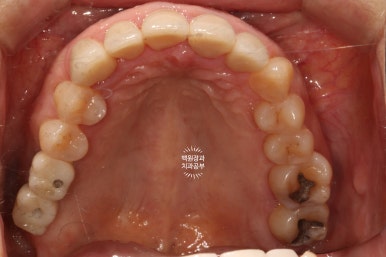

빼뚤빼뚤하기도 하면서, 금도 갖고 있었던 위 앞니들은 뒤에서 보면 이렇게 어둑하니.. 충치까지도 잘 보였습니다.

오른쪽 위 어금니 2개가 비어있어, 상악동 뼈이식술을 하면서 임플란트 2개를 심어드렸습니다.

이 것은 치주과 전문의인 제 작품입니다!! 두 명의 전문의가 상주하는 치과이지요 :)

임플란트 2차 수술을 마칠 당시, 상악동 뼈이식술을 했던 부위가 훨씬 확연하게 드러나는 것을 보실 수 있을거에요.

짜잔! 이렇게 임플란트까지 아주 예쁘게 마무리가 되었었답니다.

교합면에서 보았을 때 제작해드렸던 임플란트 크라운도 깔끔하게 잘 관리하고 계셨습니다.

이렇게 잘 쓰고 계신 모습을 보면 정말정말로 치과의사로써 큰 보람을 느낍니다 :)

3년이 지나니 상악동 뼈이식술을 했던 곳은 이제 거의 내 뼈와 하나가 된 것처럼 예쁘게 성숙된 모습을 보여주고 있고, 앞니 지르코니아 크라운은 꼼꼼히 관리해주신 덕분에 충치 하나 없이 신경치료 하지 않았음에도 아주 잘~ 쓰고 있는 모습을 확인할 수 있었습니다!